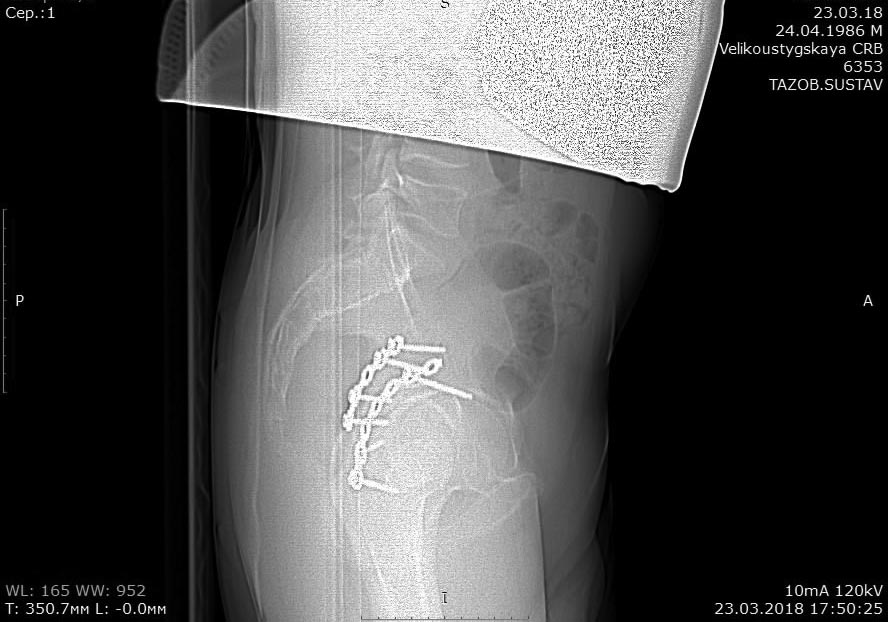

Травма в 2015 году. Водитель, попал в ДТП. Первично повреждение печени, перелом локтевой кости слева. Перелом задней колонный и задней стены левой вертлужной впадины. По экстренным показаниям выполнялась лапаротомия. Синтез задней колонны и задней стены через 13 дней через доступ Кохера-Лангенбека. Гладкий послеоперационный период. Выписан на амбулаторное лечение через 15 дней после операции. После выписки к нам не обращался, так как является жителем другого региона. Обратился через 2,5 года с жалобами на боли в области левого тазобедренного сустава.

На РКТ таза - перелом сросся. Отмечается кисты в области верхнего полюса головки бедра. Пластина фиксирующая задний край соприкасается с задними отделами головки бедра (видимо произошел частичный лизис костного края).

Планируется удаление металлоконструкции из заднего доступа